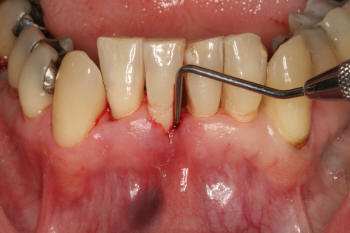

Grado 1 |

Los

dientes y los sitios seleccionados para aplicar

el índice de hemorragia simplificado son los mismos que los tomados en el

índice gingival.